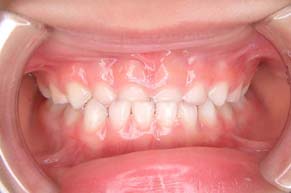

正面から観たところです。

全て乳歯です。反対咬合です。まだ幼児なので、お子様にかかる負担などをよく考えた上で、治療します。